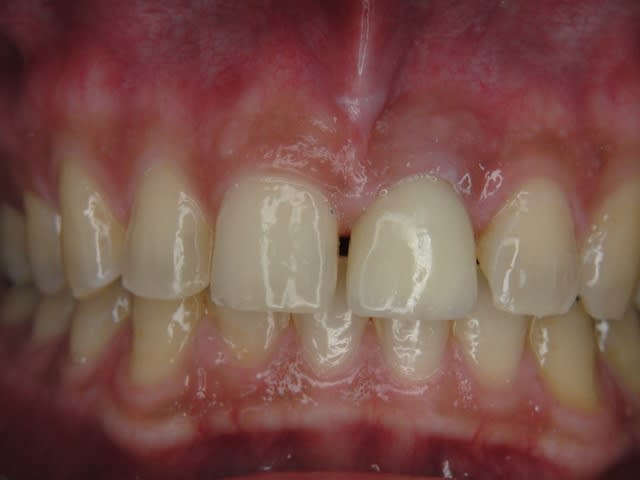

J'ai de tout en boutique..jeune homme 25 ans accident de piscine choc sur la bordure ( fêlure existante..fistule), extraction le jour même, temporisation 4 mois (avec un bout de trombone) Monobloc 16mm 60N, prep cap zircone droit 2/2 provisoire ion, temporisation 3 mois ceramo ceram..

J'ai de tout en boutique..jeune homme 25 ans accident de piscine choc sur la bordure ( fêlure existante..fistule), extraction le jour même, temporisation 4 mois (avec un bout de trombone) Monobloc 16mm 60N, prep cap zircone droit 2/2 provisoire ion, temporisation 3 mois ceramo ceram.. suite des photos :)

La gencive reste à cette place là ? Elle ne remonte pas après quelques années ?

Au contraire..si tu regarde attentivement les radios tu veras qu'en quelques mois il y a une néoformation osseuse autour des micros spires. On voit un manque le jour de la pose et plus d'os avec la Procera. Volontairement j'ai pas plus enfoncé l'implant ..Si j'avais ouvert j'aurai bousillé tout le potentiel cicatriciel..Charon l'a démontré depuis longtemps en paro. Aux patient je leur explique que "Ouvrir c'est comme tondre le gazon avec un motoculteur" .

Donc il y maintien et renfort du parodonte.

Si à ça tu rajoutes "l'amitié" de la gencive avec le zircone il n'y a pas de raisons de perdre quoi que ce soit..